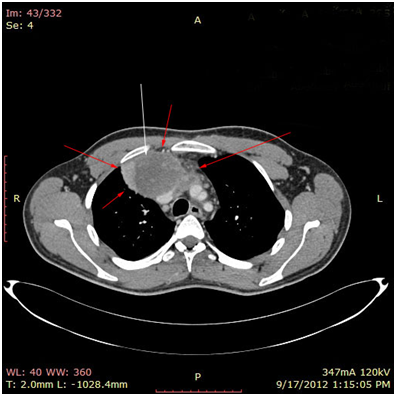

Bild 2 CT – axial plan of a large Yolk sac tumor in the anterior mediastinum invading the art. Carotis communis. White arrow pointing low attenuation foci, suggesting central necrosis.

The 1st case we report is of a 22-year-old Caucasian male, who was admitted to our hospital with a 3-days history of progressive dyspnea on exertion, neck swelling, fatigue, persistent chest pain, pyrexia, and a cough that was occasionally productive of blood. The physical examination revealed a heart rate of 115 beats per minute (Sinus Rhythm), a respiratory rate of 25 breaths per minute and superficial vascular distention over the neck. Laboratory studies revealed elevated serum α-fetoprotein (AFP) (5380 IU/ml) and D-dimer (481ng/ml). A chest X-ray in the poster - anterior view, upon admission, depicted a suggestive right upper mediastinal mass (Bild 1). Radiography was followed by contrast-enhanced CT scan that revealed a large, homogeneous mediastinal mass crossing into the anterior mediastinum and compressing – encasing the superior vena cava. It also showed signs of thrombosis of the left brachiocephalic vein, and multiple filling defects at the left pulmonary artery indicating embolism. Subcarinal lymphadenopathy, as well as enlarged lymph nodes of the right hilum was present (Bild’s 2-5). On median sternotomy, a large non resectable tumor was observed involving the in nominate vein and the superior vena cava (Bild 6). Great care was taken to remove as much tumor mass as possible. To decompress the superior vena cava, we had to perform an extensive resection and reconstruction of the cephalad part of the superior vena cava using homolog pericardium.A histopathological examination of a section of the mass revealed a mixed NSGCT (embryonal yolk sac/endodermal sinus tumour), containing also elements of embryonal carcinoma (Figure 1-6).The patient was placed on cisplatin-based chemotherapy (BEP regimen: cisplatin 50mg/m2 on days 1-2, etoposide 165mg/m2 on days 1-3, bleomycin 30U on days 1, 8, and 15, every 3 weeks). Tumor markers were elevated for a-FP (214ng/mL) and normal for β-HCG. The patient completed 4 cycles of chemotherapy and the subsequent chest CT (Bild 7) revealed a partial remission of the mass (decrease>50% of the size). The a-FP was normal as well as the β-HCG. The remaining mass was inoperable so the patient was started on salvage chemotherapy with the TIP (paclitaxel, ifosfamide, ciplatin) regimen for 4 cycles. The post-chemo chest CT showed stable disease and the patient was referred to radiation oncologists for radiotherapy of the remaining tumor. Three months later af P was found elevated and the CTs revealed multiple brain metastases. Whole brain radiation was performed and the patient was placed on gemcitabine (d1 and d8 every 21 days). Two months later the neurologic status deteriorated with new brain metastases and the patient passed away (19 months after the diagnosis).